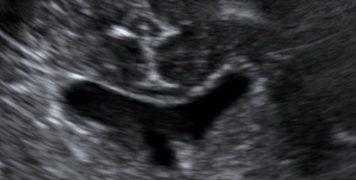

Casi del Mese di Dicembre 2024

Cari soci, finalmente on line le soluzioni dei casi del mese di Dicembre. Grazie a Sara Zullino e Mara Albanese!! Caso 1 - video [pdf-embedder url="https://www.sieog.it/wp-content/uploads/2024/12/Casodelmese_Dicembre2024caso-risposte_gineco.pdf"...